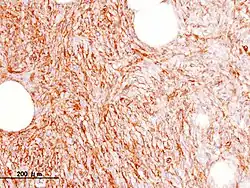

- Immunohistochemia

Włókniakomięsak guzowaty skóry wykazuje wyraźną ekspresję CD34[32]. Stwierdzenie ekspresji CD34 wspiera rozpoznanie tego mięsaka, ale marker jest obecny w wielu typach histologicznych mięsaków tkanek miękkich[6]. Ekspresja CD34 jest przydatną w różnicowaniu z guzem histiocytarnym włóknistym (benign fibrous histiocytoma)[32]. Ponadto stwierdza się silną ekspresję apolipoproteiny D, która również może być przydatna w różnicowaniu z guzem histiocytarnym włóknistym[6][33][34]. Ekspresja CD99 jest zmienna, czasem występuje ogniskowa ekspresja SMA, a reakcja dla S100, czynnika XIIIa, stromelizyny III jest ujemna[6][7].